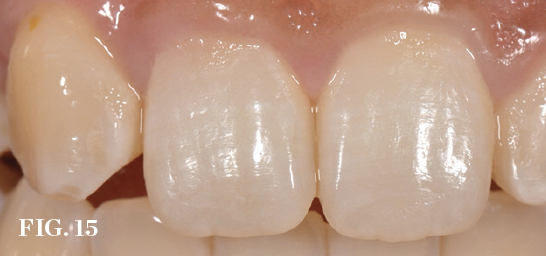

(15.) Preoperative view of a central incisor undergoing resorption (tooth No. 8). Incisionless or minimally invasive procedures can potentially enhance thesoft-tissue anatomy.

Figure 15

Flapless Techniques

When possible, incisionless implant placement should be used to minimize the bone changes and midfacial tissue recession associated with periosteal flap elevation.22 However, contour modifications necessitating marginal incisions or apical mucosal access approaches to apply bone grafts are often required to compensate for extraction-induced contour changes. In a recent prospective study, Naldini and colleagues reported superior bone volume results when flapless contour augmentation with a xenogeneic bone graft/membrane was used in conjunction with immediate implant placement (Figure 15 through Figure 18).23